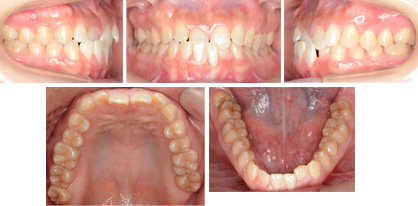

来院時の写真

気になっている点(主訴): 反対咬合 下顎前突

前歯の反対咬合(下顎前突)をリンガルブラケット(裏側矯正)で矯正治療を希望されて来院されました。

小臼歯などを抜歯せずに治療をおこないました。非抜歯での治療は約1年が目安になります。

骨格性下顎前突

骨格的な原因もありました。叢生などデコボコはありませんでした。こういった場合は前歯の傾斜角度が重要になります。リンガルブラケットを用いて周囲の人に気づかれないように治療する事ができました。

治療に関してのリスクは予想していません。ありませんでしたが、下顎左側中切歯がわずかに歯肉退縮していました。これは咬合性外傷(こうごうせいがいしょう)によるものです。かみ合わせが反対になっているためにこの歯に想定外の力が加わったために耐えられなく起きた事です。このまま長期化すると歯にとってはよくありません。